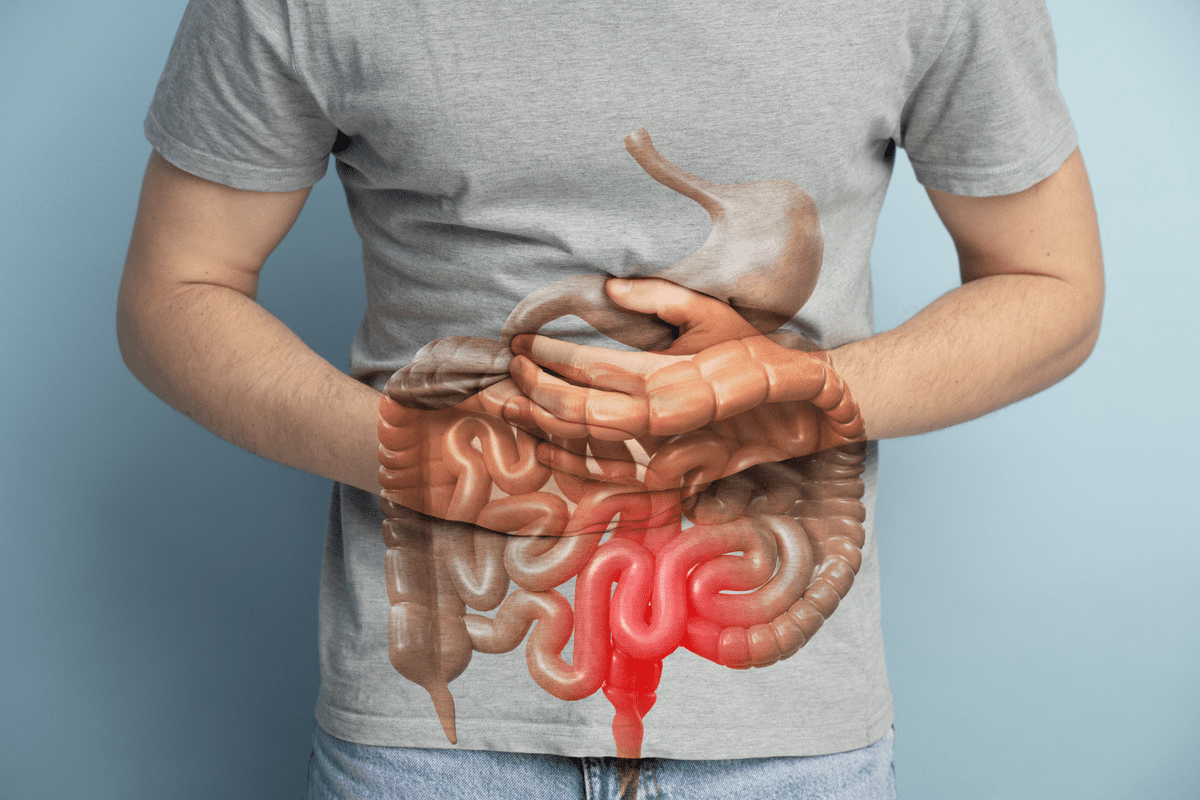

Muscle Weakness and Motor Symptoms

A herniated disc can cause muscle weakness by pressing on nerves. This can make it hard to do everyday tasks.

How Herniated Discs Affect Muscle Strength

When a disc herniates, it can press on nerves. This can mess up the signals to muscles, causing weakness. The weakness’s extent depends on the herniation’s location and severity.

Nerve compression is key in muscle strength. The more compression, the more weakness.

The image below shows the complex link between nerve compression and muscle weakness. It requires careful diagnosis.